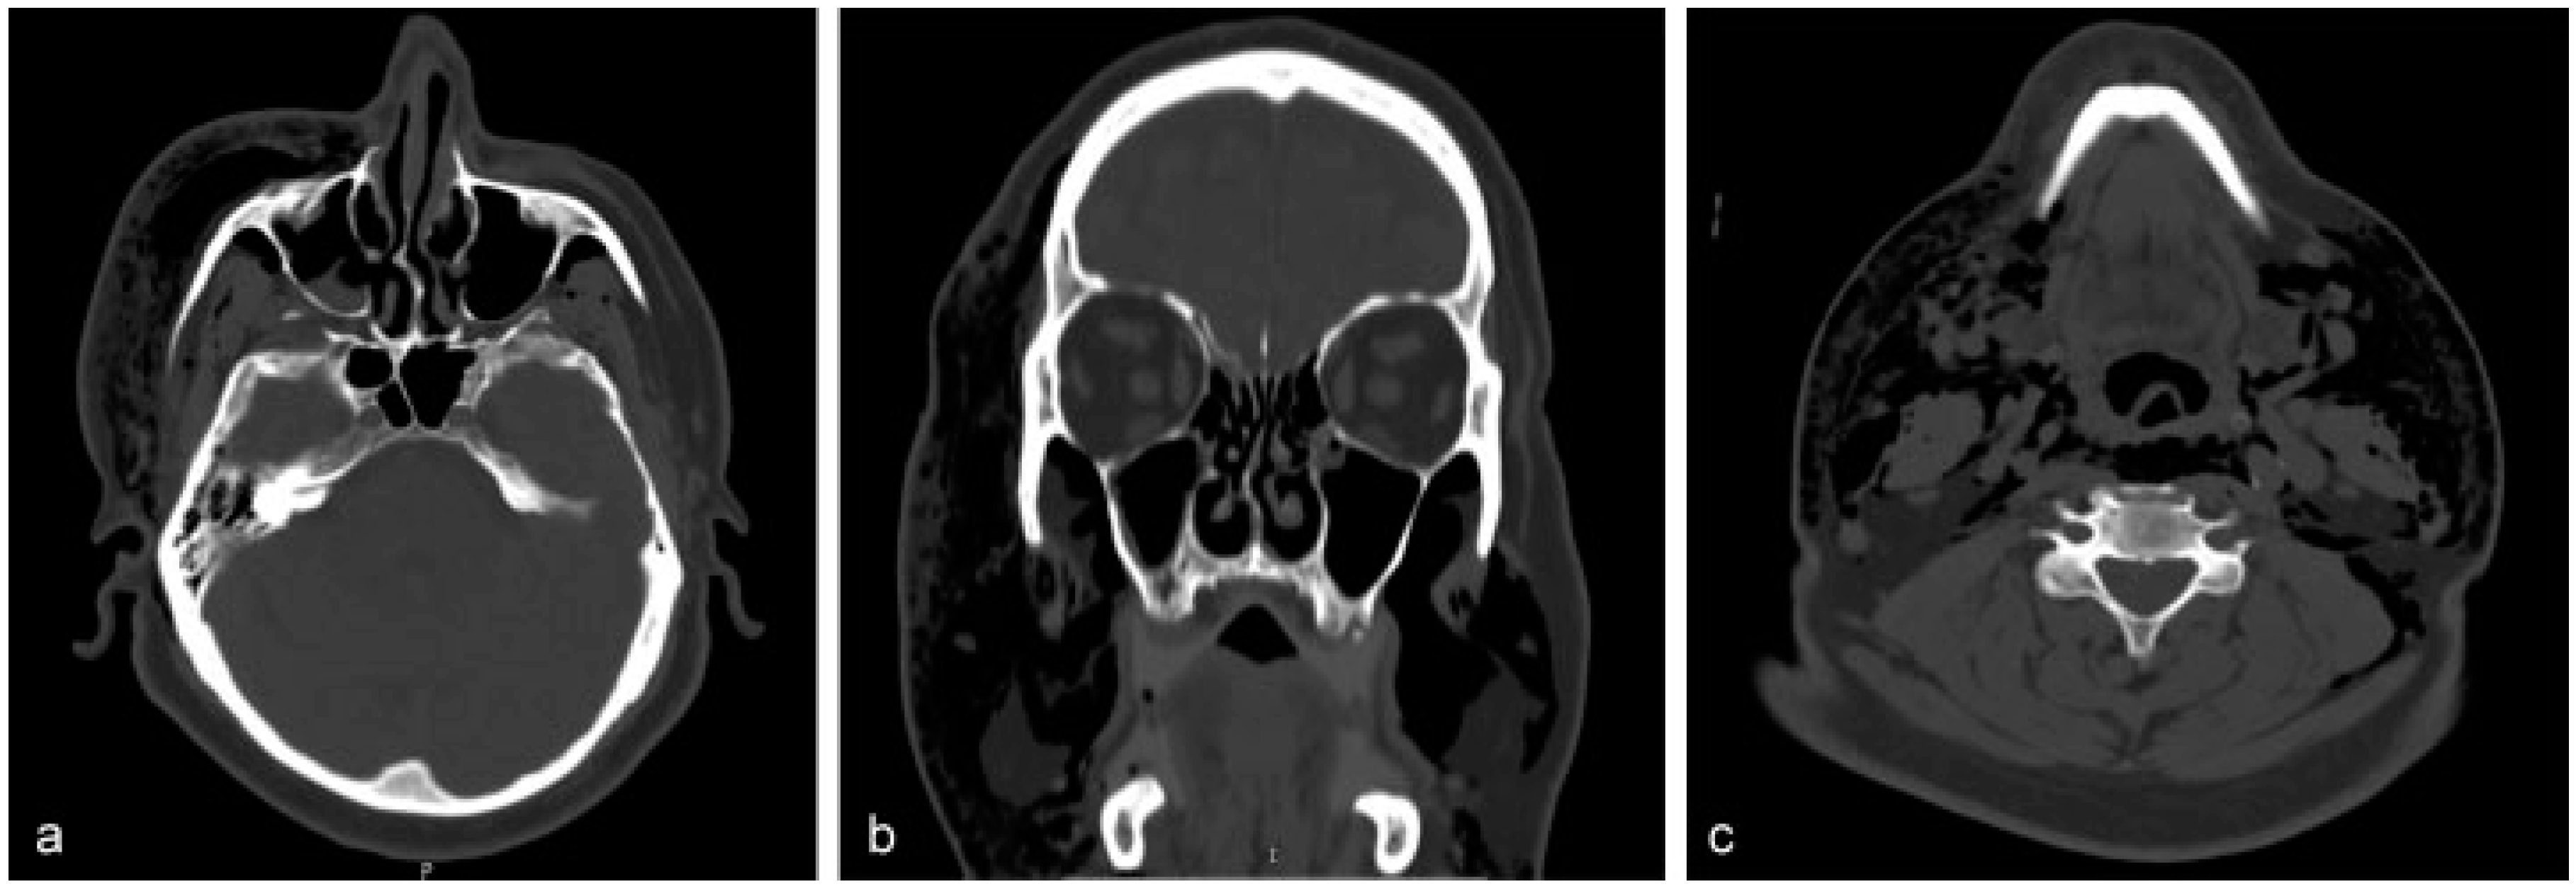

Case Report